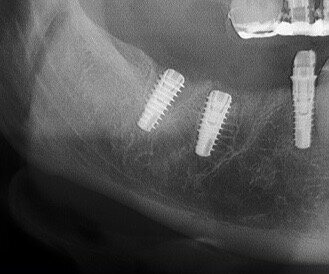

Fig. 14 - Controllo rx Post-chirurgico time 0: Si valuta bene la posizione intra-alveolare degli Impianti Multysytem.

Fig. 15 - Controllo rx a 120 gg. Gli impianti sono integrati nella nuova sede formatasi.